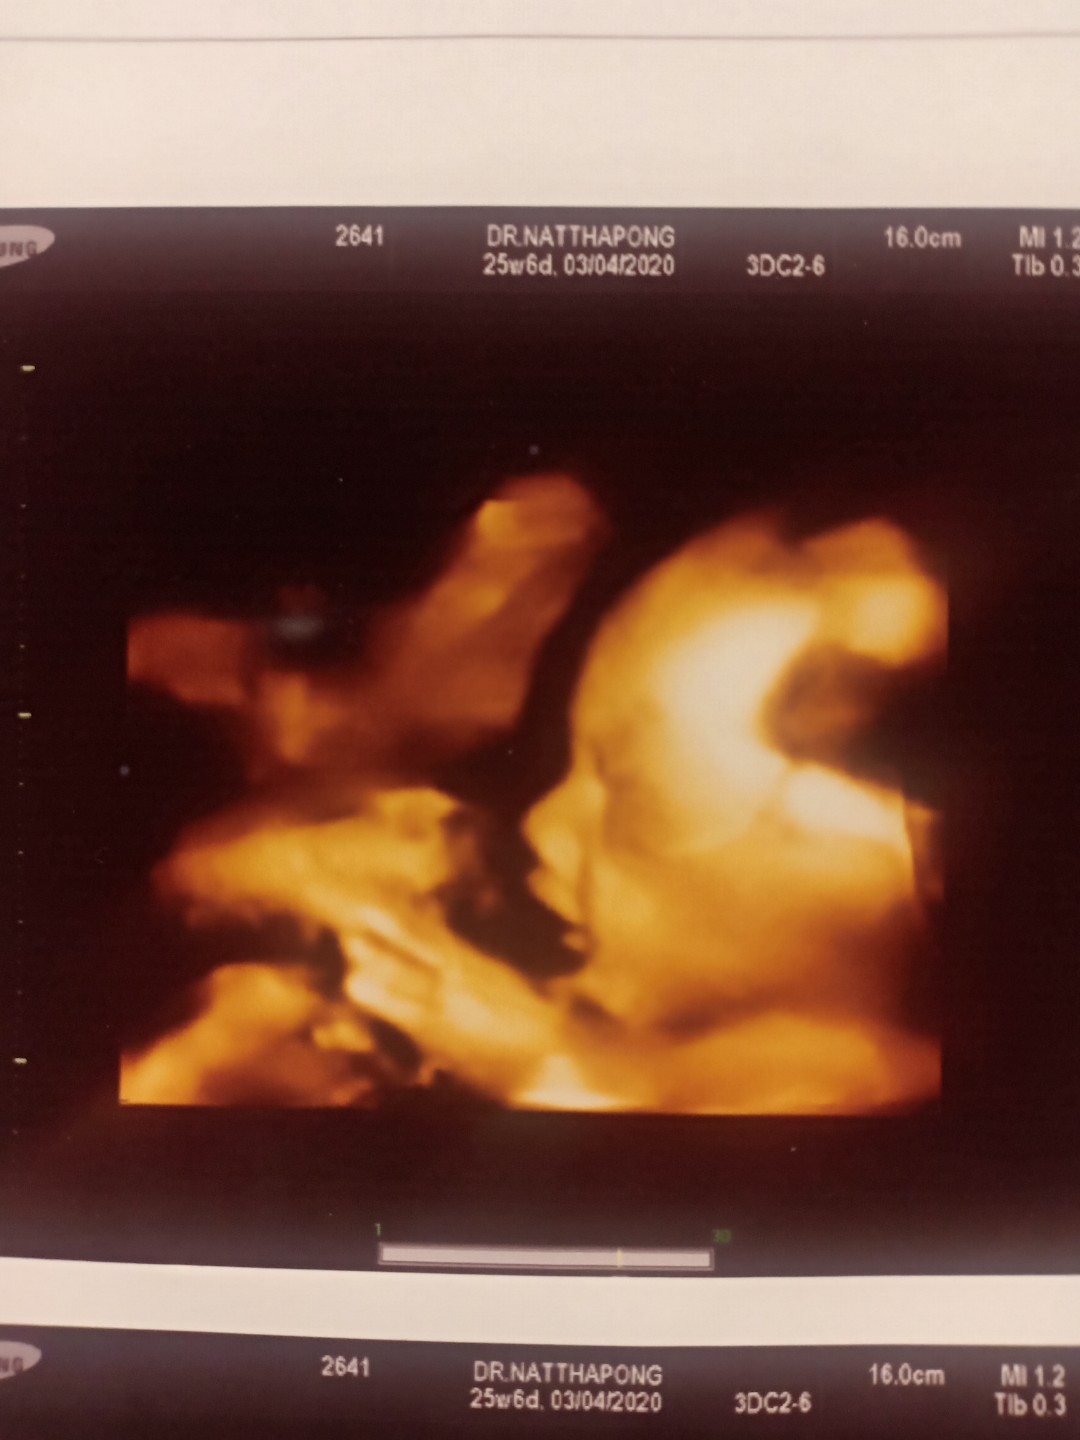

ลูกชายบ้านนี้ 26w ครับผม รอลุ้นว่า ออกมาจมูกจะโด่งมั้ยครับ